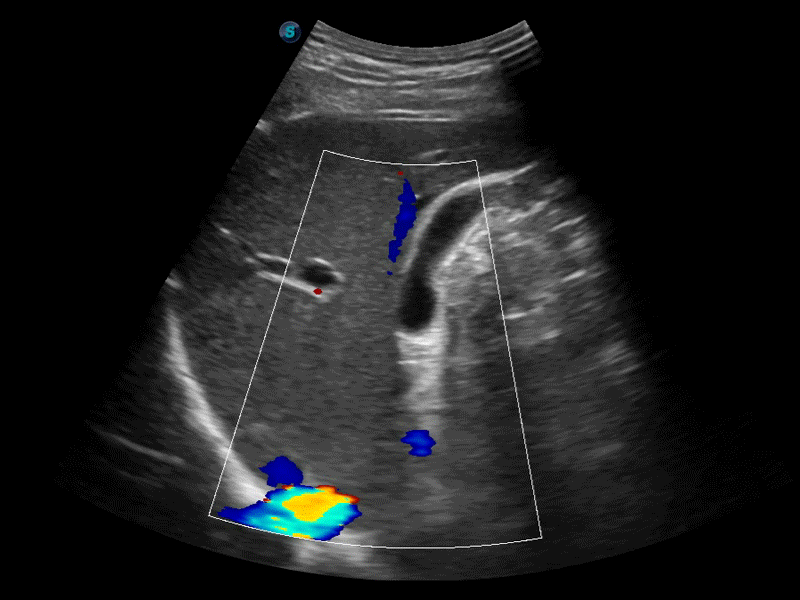

凸阵、线阵和相控阵探头进行实时扫描时,开启扩展成像模式,可以扩展超声图像视野,以便更完整地查看大的病灶或组织器官的解剖结构。

通过色彩血流和实时宽景相结合,可观察到完整的静脉或动脉的血流,方便医生检查。实时扫查过程中,如有任何操作失误也可以很容易地进行回扫擦除,而不会中断扫查。